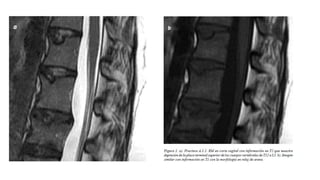

• Hematomielia o contusión medular por medio de la RMN. (mal pronostico)

SINDROME CENTRAL DELA MEDULA O DE SCHNEIDER • Síndrome medular incompleto mas frecuente, lesión de materia blanca periférica. • Perdida de la función motora con predominio en extremidades superiores. • Lesión generalmente exclusiva de la región cervical • Causa: Hiperextensión en un canal cervical estrecho congénito o adquirido. • Hematomielia o contusión medular por medio de la RMN. (mal pronostico)